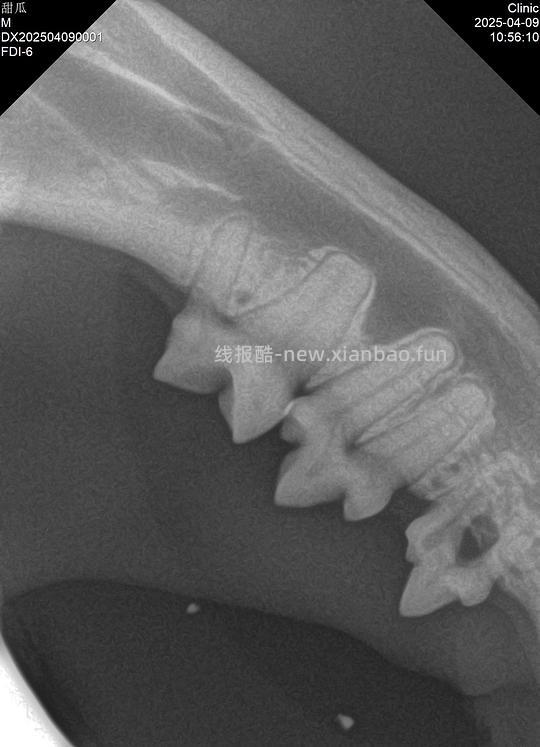

Type1可能和牙周病相关(好好刷牙对1型还是有帮助的),完整拔牙;Type2特应性,原因未知,甜瓜407号牙就是2型,牙冠切除;Type3是T1+T2,手术方案由医生评估,甜瓜307号牙是3型,完整拔除。

牙吸收无法阻止也无法预测,这意味着拔除病变牙后其他牙未必一定会吸收。所以我选择听医生的专业意见,处理影像学中确认牙吸收的坏牙307和407(这两颗牙通常是牙吸收最先发生的位置),因为106、206的牙龈也有红肿迹象,拔了也不影响咬合,虽然目前不是牙吸收,在我的要求下医生同意拔除了。309和409两颗下牙或许因为清洁不到位,有不同程度的早期牙周病,但只要做好维护不至于拔除,我会每天好好清洁,遵循医嘱,在甜瓜十岁前再拍一次牙片,如果牙况恶化,会根据届时情况选择合适的牙科手术方案。